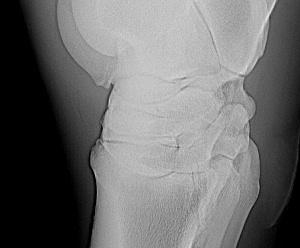

Another x-ray:

Leg #3

An addendum to the above. I have moved the radiograph images to a larger screen and viewing them it appears all the fragments are off the back of the talus and may communicate with the talocaneal joint (correction off the back of the calcaneus and communicates with the talocrural joint~DrO) cand have minimal effect on the stability of the joint. Does the veterinarian who has the originals agree?

Well, Janice you do help buy baby a new pair of shoes but I have to correct my anatomy above, this is most likely off the calcaneus and not the talus and communicates with the talocrural joint not the talocalcaneal joint by way of the proximal intertarsal joint. I must of had talus on the brain. The gist of my comments on prognosis and treatment still apply. I do think a flexed lateral and flexed dorsolateral-posteriomedial and a skyline view of the plantar surface of the talus would further eludicate whether the 4th tarsal bone is involved or intraarticular bone is involved.